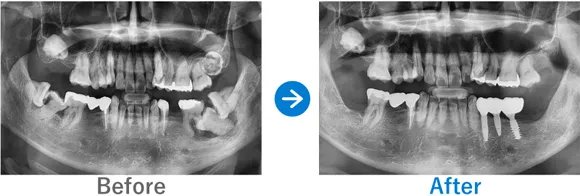

歯が1本もない状態、10年以上前から上下総義歯(総入れ歯)

上顎ALLON6、下顎ALLON4、

リオペ上顎追加埋入ザイゴマインプラント2本

治療結果

上下ALLON4、右上5、左上3、リオペザイゴマインプラント2本追加順調の経過、治療終了、メンテナンス来院。インプラントで噛めるようになり、喜んでいただいた。しっかりセルフケアを頑張っておられます。お顔の表情も明るくなられて、気持ちも前向きに過ごされています。